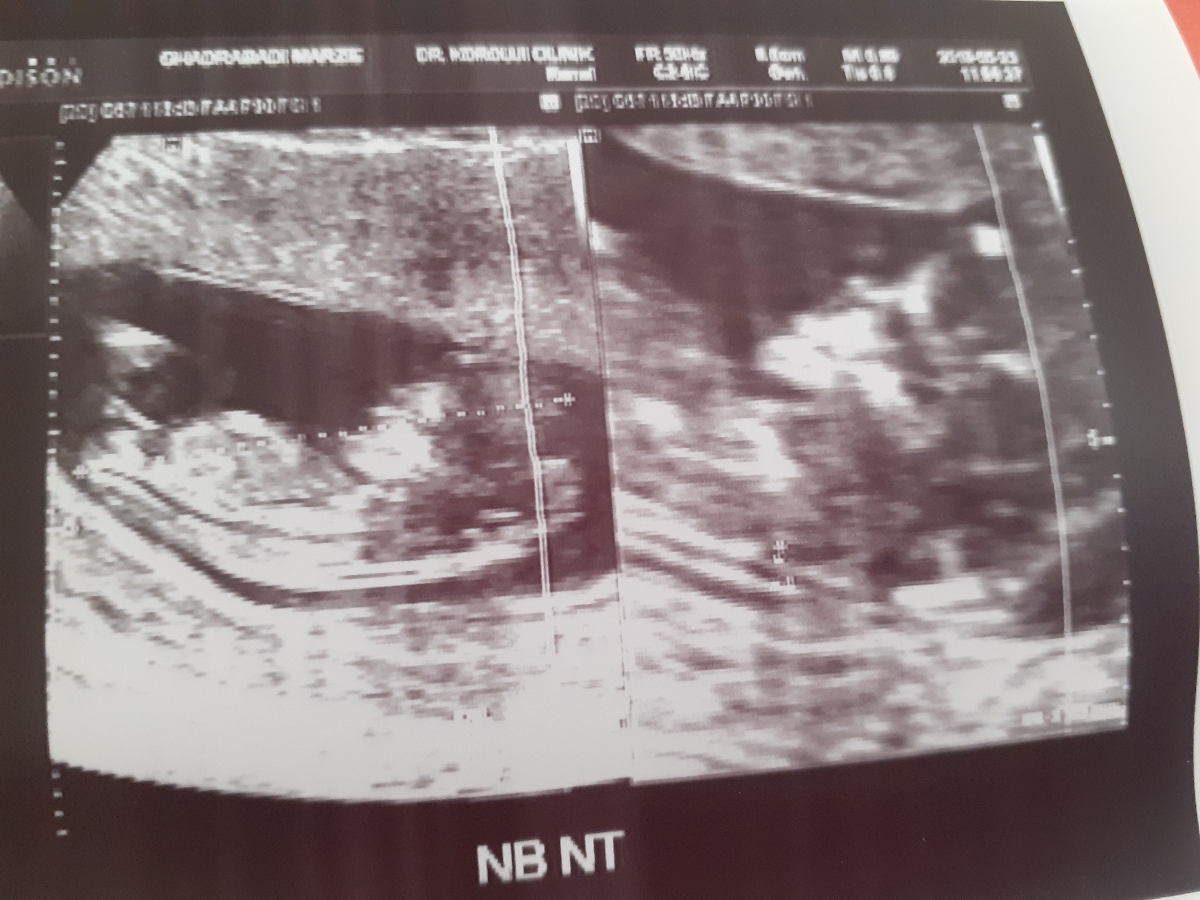

سنوگرافی nt تفسیر 🙏😘 دکتر تفسیر کنید واسم سنو

ان تی ک خوبه ان بی هم ک دیده شده

سلام همه موارد خوبه یک دور پیچیدن بند ناف دور گردن جنین مشکلی ندارد. خود به خود با یک چرخش باز میشه. طول سرویکس خیلی خوبه ، عدد ان تی هم خوبه ، فقط جفت مارژینال است که باید استراحت نسبی را داشته باشید